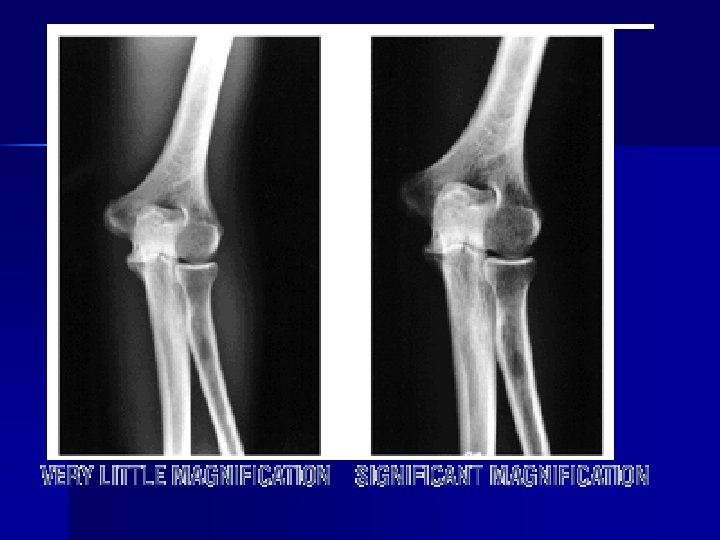

MAGNIFICATION n TUBE CLOSE TO THE PART (SID) n PART FAR FROM THE CASSETTE (OID)

Size Distortion & OID n If source is kept constant, OID will affect magnification n As OID , magnification n The farther the object is from the film, the more magnification

• In terms of recorded detail and magnification the best image is produced with a • ______ OID & _____ SID

Minimal magnification small OID Magnification large OID

Size Distortion & SID n Major influences: SID & OID n As SID , magnification n Standardized SID’s allow radiologist to assume certain amt. of magnification factors are present n Must note deviations from standard SID